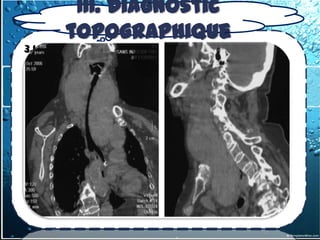

b) TDM thoracique avec injection de

produit de contraste

permet de caractériser la masse

de visualiser ses relations avec les

structures avoisinantes, d’identifier la

composition de la masse (kyste, tissu

,graisse, vaisseau)

permet également la meilleure

approche en vue de la biopsie diagnostic

IRM n’est utilisé que pour mieux évaluer

l’extension de l’invasion vasculaire ou

cardiaque

Le seul avantage de l'IRM , confirmer la

nature liquidienne d'une lésion dont la

plage est de densité élevée en TDM, ex:

kystes bronchogéniques

IRM > TDM pour l'étude des masses du

médiastin postérieur, pour préciser une

éventuelle extension intracanalaire d'une

tumeur neurogène ou d'un abcès